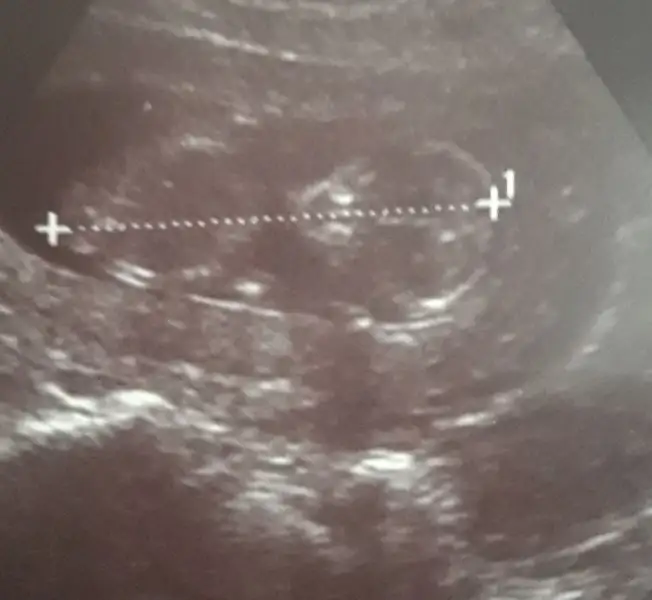

Kız gibi geldiBide buna bakin hanimlar size zahmet tahminleriniz

Kese ye göre yorum yapıyoruz. Koymuş muydun?

Kese ye göre yorum yapıyoruz. Koymuş muydun?Bana da tahmin lazim cok merak ediyorum cinsiyeti![]()